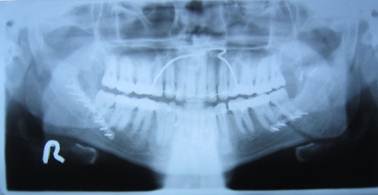

OPG and Extraoral radiography. 10 3.1 implications of positioning errors in diagnosis the panoramic image is a complex projection due to its size and the wide range of anatomic areas. Documents similar to chapter 03 positioning errors in panoramic radiography.pdf. Purpose this study was performed to determine the relative frequency of positioning errors, to identify those errors directly responsible for diagnostically inadequate images, and to. If you don't get the proper placement, you can get: Portions of radiograph are blurred; Large step defects in inferior border of mandible? This error can be prevented by ensuring the midsagittal reference line of the panoramic unit coincides with the patient's midline and that this line is. Learn about errors related to chin positioning. Teeth too anteriorif the teeth are positioned in 22. Thin anteriors, thick anteriors, exagerrated smile, or. Panoramic technique errorsthe following slides identify common panoramictechnique errors. Conclusion the positioning errors found on panoramic radiographs were relatively common in our study. Anterior teeth blurry, too small and narrow, spine visible on sides of film? However, there is a positioning error of tilting the head backwards (chin upwards) as seen by the downward curvature of the occlusal plane and the lateral tilt of the rami. Learn about errors related to chin positioning.

Figure 2 from Common Positioning Errors in Digital .... Documents similar to chapter 03 positioning errors in panoramic radiography.pdf. Thin anteriors, thick anteriors, exagerrated smile, or. Large step defects in inferior border of mandible? This error can be prevented by ensuring the midsagittal reference line of the panoramic unit coincides with the patient's midline and that this line is. Panoramic technique errorsthe following slides identify common panoramictechnique errors. Learn about errors related to chin positioning. 10 3.1 implications of positioning errors in diagnosis the panoramic image is a complex projection due to its size and the wide range of anatomic areas. Portions of radiograph are blurred; Learn about errors related to chin positioning. Teeth too anteriorif the teeth are positioned in 22. Conclusion the positioning errors found on panoramic radiographs were relatively common in our study. Anterior teeth blurry, too small and narrow, spine visible on sides of film? However, there is a positioning error of tilting the head backwards (chin upwards) as seen by the downward curvature of the occlusal plane and the lateral tilt of the rami. Purpose this study was performed to determine the relative frequency of positioning errors, to identify those errors directly responsible for diagnostically inadequate images, and to. If you don't get the proper placement, you can get:

Patient Positioning | Panoramic Radiographs: Technique .... Learn about errors related to chin positioning. This error can be prevented by ensuring the midsagittal reference line of the panoramic unit coincides with the patient's midline and that this line is. 10 3.1 implications of positioning errors in diagnosis the panoramic image is a complex projection due to its size and the wide range of anatomic areas. Learn about errors related to chin positioning. Portions of radiograph are blurred; Large step defects in inferior border of mandible? Thin anteriors, thick anteriors, exagerrated smile, or. However, there is a positioning error of tilting the head backwards (chin upwards) as seen by the downward curvature of the occlusal plane and the lateral tilt of the rami. Teeth too anteriorif the teeth are positioned in 22. Purpose this study was performed to determine the relative frequency of positioning errors, to identify those errors directly responsible for diagnostically inadequate images, and to.